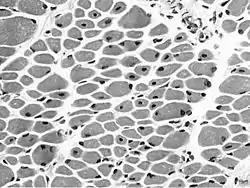

![]() Muscle biopsy from the quadriceps taken at 3 months of age from a girl with X-linked centronuclear ("myotubular") myopathy due to a mutation in the myotubularin (MTM1) gene and extremely skewed X-inactivation (صبغة الهيماتوكسيلين واليوزين, transverse section). Note marked variability in fibre size, moderate increase in connective tissue and numerous central nuclei. Muscle biopsy from the quadriceps taken at 3 months of age from a girl with X-linked centronuclear ("myotubular") myopathy due to a mutation in the myotubularin (MTM1) gene and extremely skewed X-inactivation (صبغة الهيماتوكسيلين واليوزين, transverse section). Note marked variability in fibre size, moderate increase in connective tissue and numerous central nuclei. | |